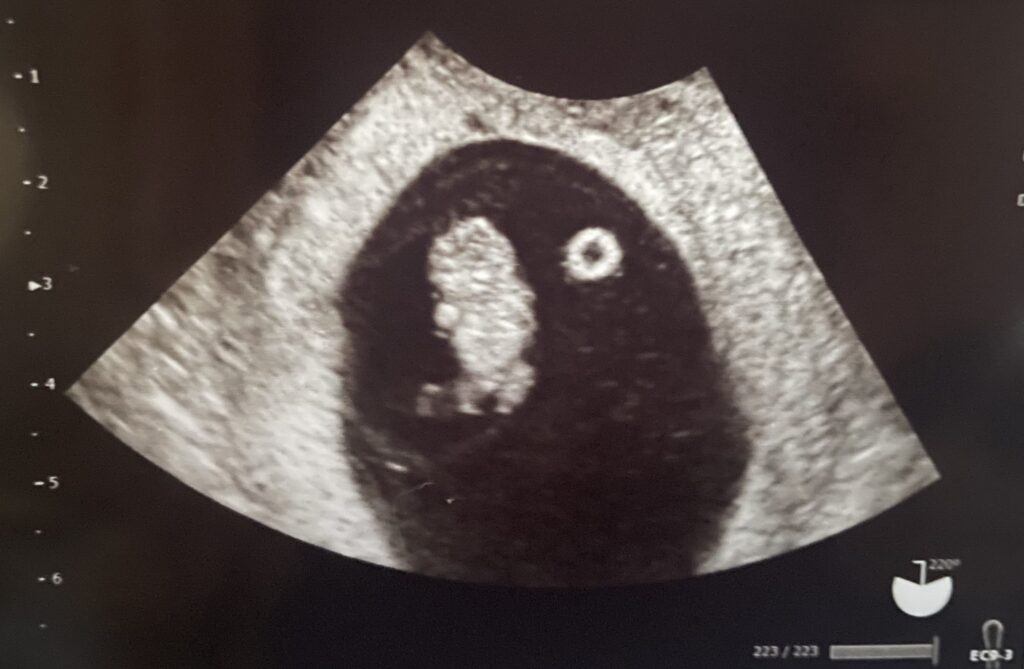

2回目の経膣エコーで赤ちゃんを確認

ってことで妊婦検診ではないので、この日は経膣エコーで赤ちゃんの確認だけ。

なんとなく元気な気がしてたけど、エコーでもちゃんと確認できて心拍もあって良かったです😅(この時だけはさっきまでの揉め事も忘れられました)

2週間前は豆粒だったのに、今はちゃんと人型になっていて感動🥺